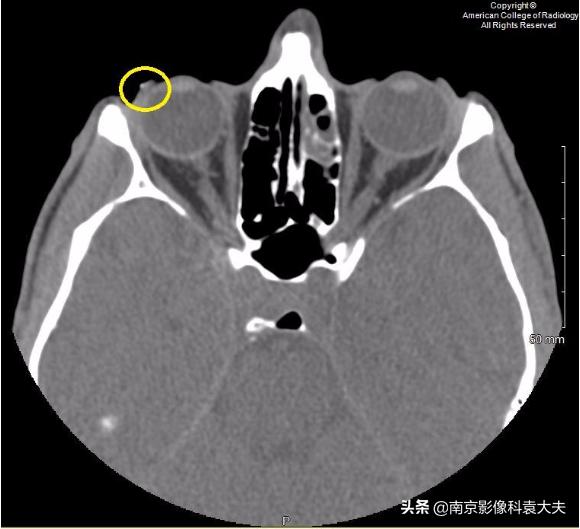

上图 眼球轴位非对比CT图像显示右侧眼睑外侧或巩膜表面可见点状异物(黄圈),发现巩膜上异物,我们应提高对角膜裂伤或其他眼球损伤的怀疑程度。